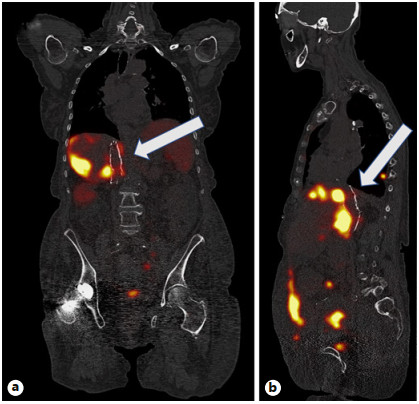

Abstract: Small bowel-origin carcinoid tumor is indolent but may metastasize relentlessly to various sites, including the liver. Over the past 9 years, we have treated a 69-year-old woman who has undergone 5 percutaneous liver ablations, 5 hepatic intra-arterial chemoembolizations, an ovarian cryoablation, and a trans-ventral hernia mesenteric cryoablation. These interventions are all related to her inoperable carcinoid malignancy. After the patient presented with swelling of the abdomen and both lower extremities, computed tomography (CT) angiography was performed, revealing a circumferential hepatic metastatic mass encasing the intrahepatic inferior vena cava (IVC) and extensive third spacing of fluids specific to the IVC distribution below the diaphragm. A venogram of the intrahepatic IVC revealed extrinsic compression causing 95% narrowing of the vessel. A balloon was advanced to the level of the lesion and inflated, increasing the caliber of the vessel. Subsequently, 2 covered aortic stent graft cuffs were deployed in an overlapping fashion within the lumen of the IVC, traversing the area of narrowing. Next, an open-cell aortic dissection stent was placed across both overlapping aortic stents from the renal veins to the hepatic veins. Following this, three 17-gauge cryoablation probes were inserted into the segment 1 intrahepatic lesions encasing the newly stented IVC via an anterior percutaneous approach. Two 10-min freeze cycles were performed with intraoperative CT imaging, demonstrating circumferential coverage of the lesions. Posttreatment venogram revealed patent stent grafts within the intrahepatic IVC, and restoration of vessel patency. No immediate postoperative complications were noted. The patient’s abdominal and lower extremity swelling resolved completely within 1 week after procedure. Two-month follow-up CT demonstrated markedly decreased size of the metastatic lesions and no adverse effects. Six- and 9-month PET-CT scans demonstrated maintained patency of the IVC stent. This palliative procedure allowed the patient to maintain good performance status and alleviated her symptoms of IVC syndrome. The radial force generated by the multiple aortic stents will ostensibly maintain the patency of the intrahepatic IVC. Cryoablation of the encasing metastatic lesion was performed with markedly decreased size of the tumor on the 2-month follow-up.